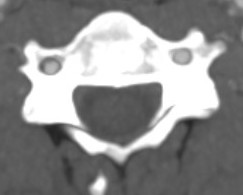

Expose Longus colli muscles anteriorly over ALL

- sympathetic chain lies on the Longus colli, just lateral to the vertebrae

- dissect between muscles in the midline

- retractors under longus colli

- expose cervical vertebrae

Cervical sympathetic trunk

Anatomy

Runs on the longus colli muscles

Consequence of injury

Horner syndrome

- ipsilateral ptosis

- ipsilateral meiosis

- anhidrosis

Incidence

Lubelski et al World Neurosurg 2020

- systematic review of 21 studies

- incidence of 0.6%

- 60% completely resolved at 1 year